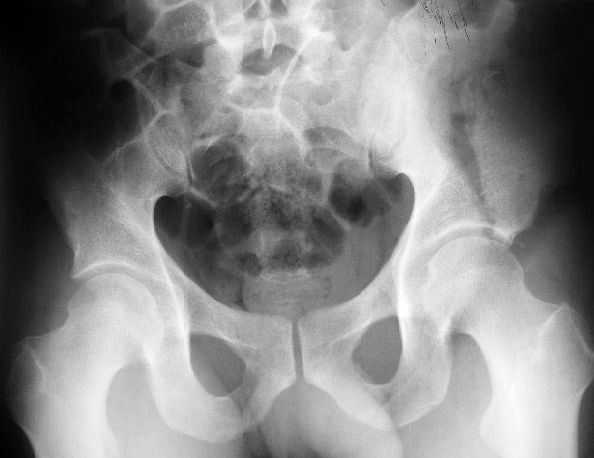

Поступил пациент после кататравмы (упал с высоты 4м). После обследования установлен Ds: Сочетанная травма. ЗТГК перелом 5-6 ребер справа. Ушиб левого леогкого. Оскольчатый перелом крыла подвздошной кости слева, со смещением. в экстренном порядке выполнена операция о/синтез таза стержневым аппаратом. Снимки прилагаются. Пациент со 2-го дня стал ходить без костылей. Из анамнеза жизни у пациента имеется гепатит В и С, с 1998г. употребляет наркотики (героин 1г в день нормальная доза). На контрольных снимках таза в аппарате смещение отломков сохраняется, да еще и стержни сломались. Подскажите ув.коллеги, как поступить в данной ситуации: оставить все как есть или добиваться репозиции в аппарате, или планировать на открытую репозицию. На сегодняшний день пациент стабилен, по анализам компенсирован. Принимает героин по другому справиться не может. С ув. Андрей